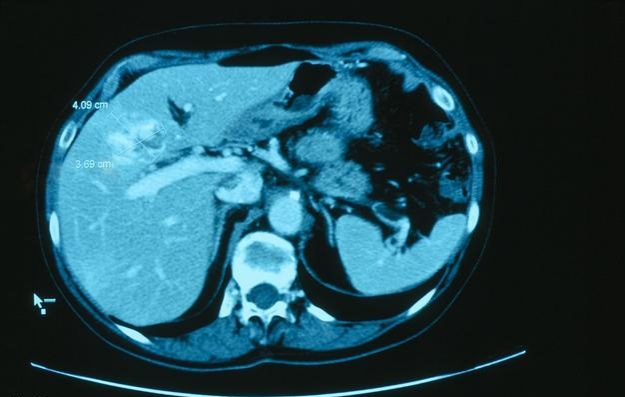

14少女被诊断为肝癌,医生再三询问,少女道出真相,令人吃惊! - 靖西市·靖西网